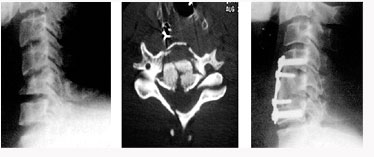

척추관 협착증의 방사선 소견